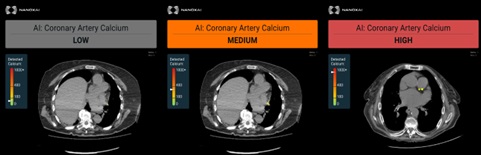

AI Cardiac Solution – HealthCCSng by Nanox.AI: Coronary artery calcium detection

AI Cardiac Solution – HealthCCSng product is a software device that automatically estimates the coronary artery calcium category from non-cardiac-gated adult CT scans. The product is aimed to leverage the high utilization of CT scans in the medical care environment (both inpatient and outpatient), including lung cancer screening programs, in order to automatically detect calcification in the coronary arteries of patients in an opportunistic manner.

• Generates three-category estimation of calcium quantity, preview axial image of the detected calcium

For patients in which calcium was detected, the user will be presented with representative images – all the slices containing the measured coronary calcifications (130 HU and above). On these images, the calcified areas will be annotated (with an option for the user to toggle on and off the annotation).